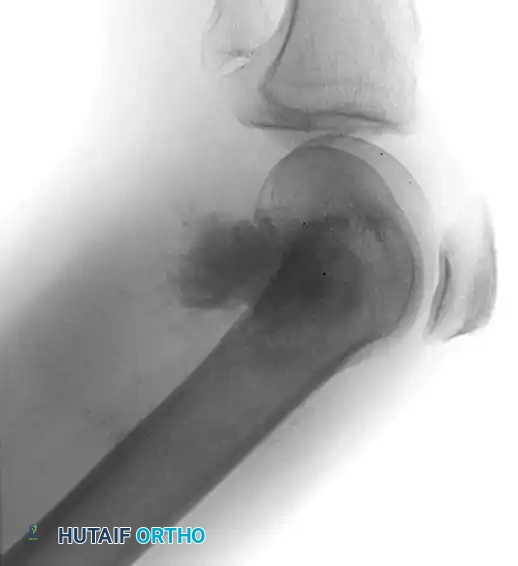

Image

Anteroposterior and lateral radiographs demonstrating a highly aggressive, mixed lytic and blastic osteosarcoma in the distal femur of a 31-year-old man, with cortical destruction and soft-tissue extension.